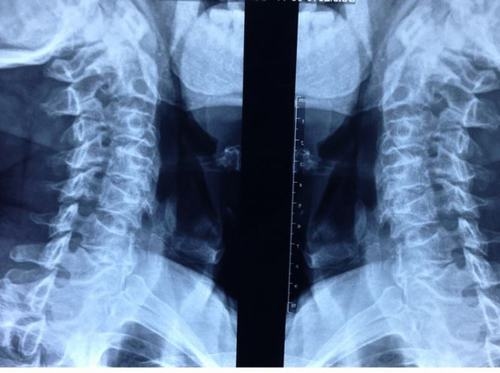

Chụp X quang giúp phát hiện tình trạng thoái hóa

Người bệnh được thăm khám lâm sàng và thực hiện các phương pháp cận lâm sàng như chụp X quang, chụp CT, MRI để đánh giá mức độ thoái hóa và biến chứng nếu có.